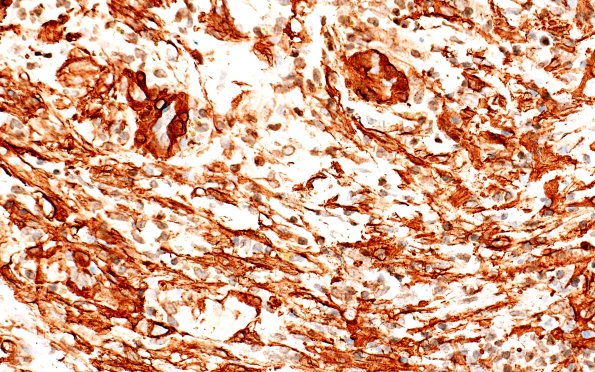

SMA immunoreactivity labels tumor cells and the microvasculature. (SMA IHC)